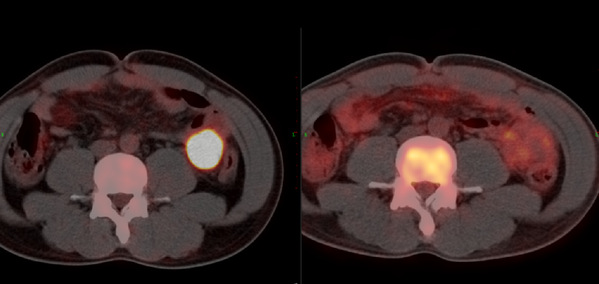

After completing the approval of various clinical studies, Prof. Huang’s team infused the patient with PD1-19bbz CAR-T cells on May 26, 2020. Later on June 9, 14 days after the reinfusion, all the indicators were normal. The patient was discharged from the hospital after assessment. PET-CT evalsuation was performed 1 month after the reinfusion. The results showed that the large mass tumor that invaded the intestinal mucosa in the original abdominal cavity had completely disappeared. And Mr. Sun has been seen disease-free for more than 2 years.

Left: before CAR-T therapy; Right: 1 month after CAR-T therapy